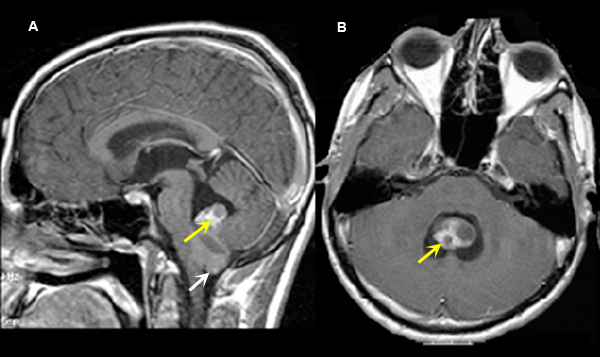

Ependymoma

Imaging findings: Figure 5

- Enhancing tumor (yellow arrow) is seen within the inferior portion of IV ventricle with tonsillar herniation (white arrow).

Final impression:

Ependymoma is a glial tumor that arises from the ependymal lining of the ventricles. Location of the tumor result in obstructive hydrocephalus. Ependymoma occur within the fourth ventricle, third ventricle and lateral ventricle, more common within the fourth ventricle. Ependymoma is more commonly seen in children than adults. However, spinal cord ependymoma is seen more in adults. |